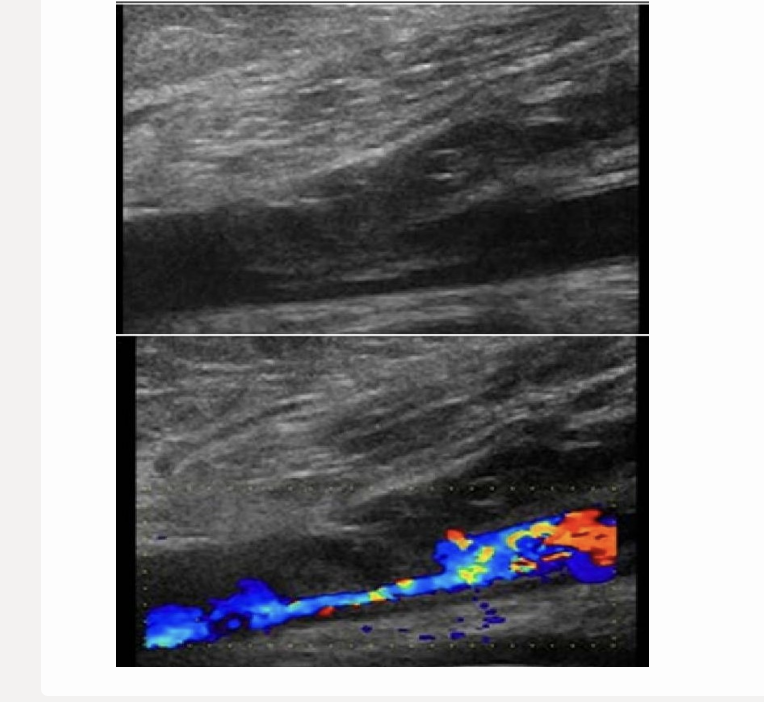

while scanning a pt after a recent car accident, you notice an arteriovenous connection in the left groin

.

how can you determine if this is related to the recent trauma or congenital abnormality

a) determine location of AV connection

b) how many connections between artery + vein

c) evaluate deep veins for associated thrombus

d) do a doppler of flow in connected vessels